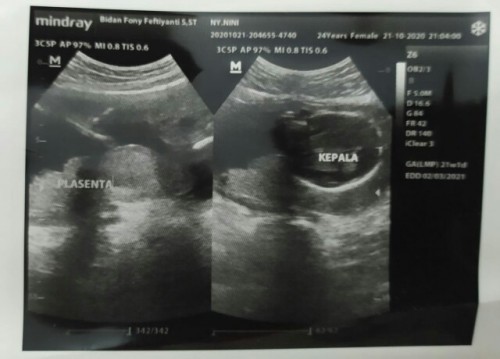

usia kehamilan ku udah 5bulan lebih tp jenis kelamin nya blm keliatan knpa ya bun. oh ya bun kata dokter plasenta saya berada dibawah deket jalan lahir apa bisa berubah ya supaya bisa lahiran normal🙁

ko nasib kt sm sih bun, kmrin paa usia 21 week aku usg ktnya posisi byinya kurg bgus dan yg bkin aku was was jg plasentanya ad d bwah. aku smpe saat ini msh kpkran aj bun tkt gbsa pindah posisi plasentanya klo msh ttp dbwh itu menyulitkan byi buat menemukan jalan lhr nantinya sdgkn aku cr info d yutub ktnya plasenta itu keadaannya melekat d rahim jd gbsa di manipulasi dengan cara kt nunging2 buat bntu rubah posisi pasenta. krn brbeda bukan janin yg mengapung d air ketuban. tp sih seiring brjlannya wktu dan usia khmln brtmbh si rahim brtmbh besar da seolah olah pasenta itu bergeser jd msh bs kemungkinan lhrn normal. smga aj y bun ad keajaiban..